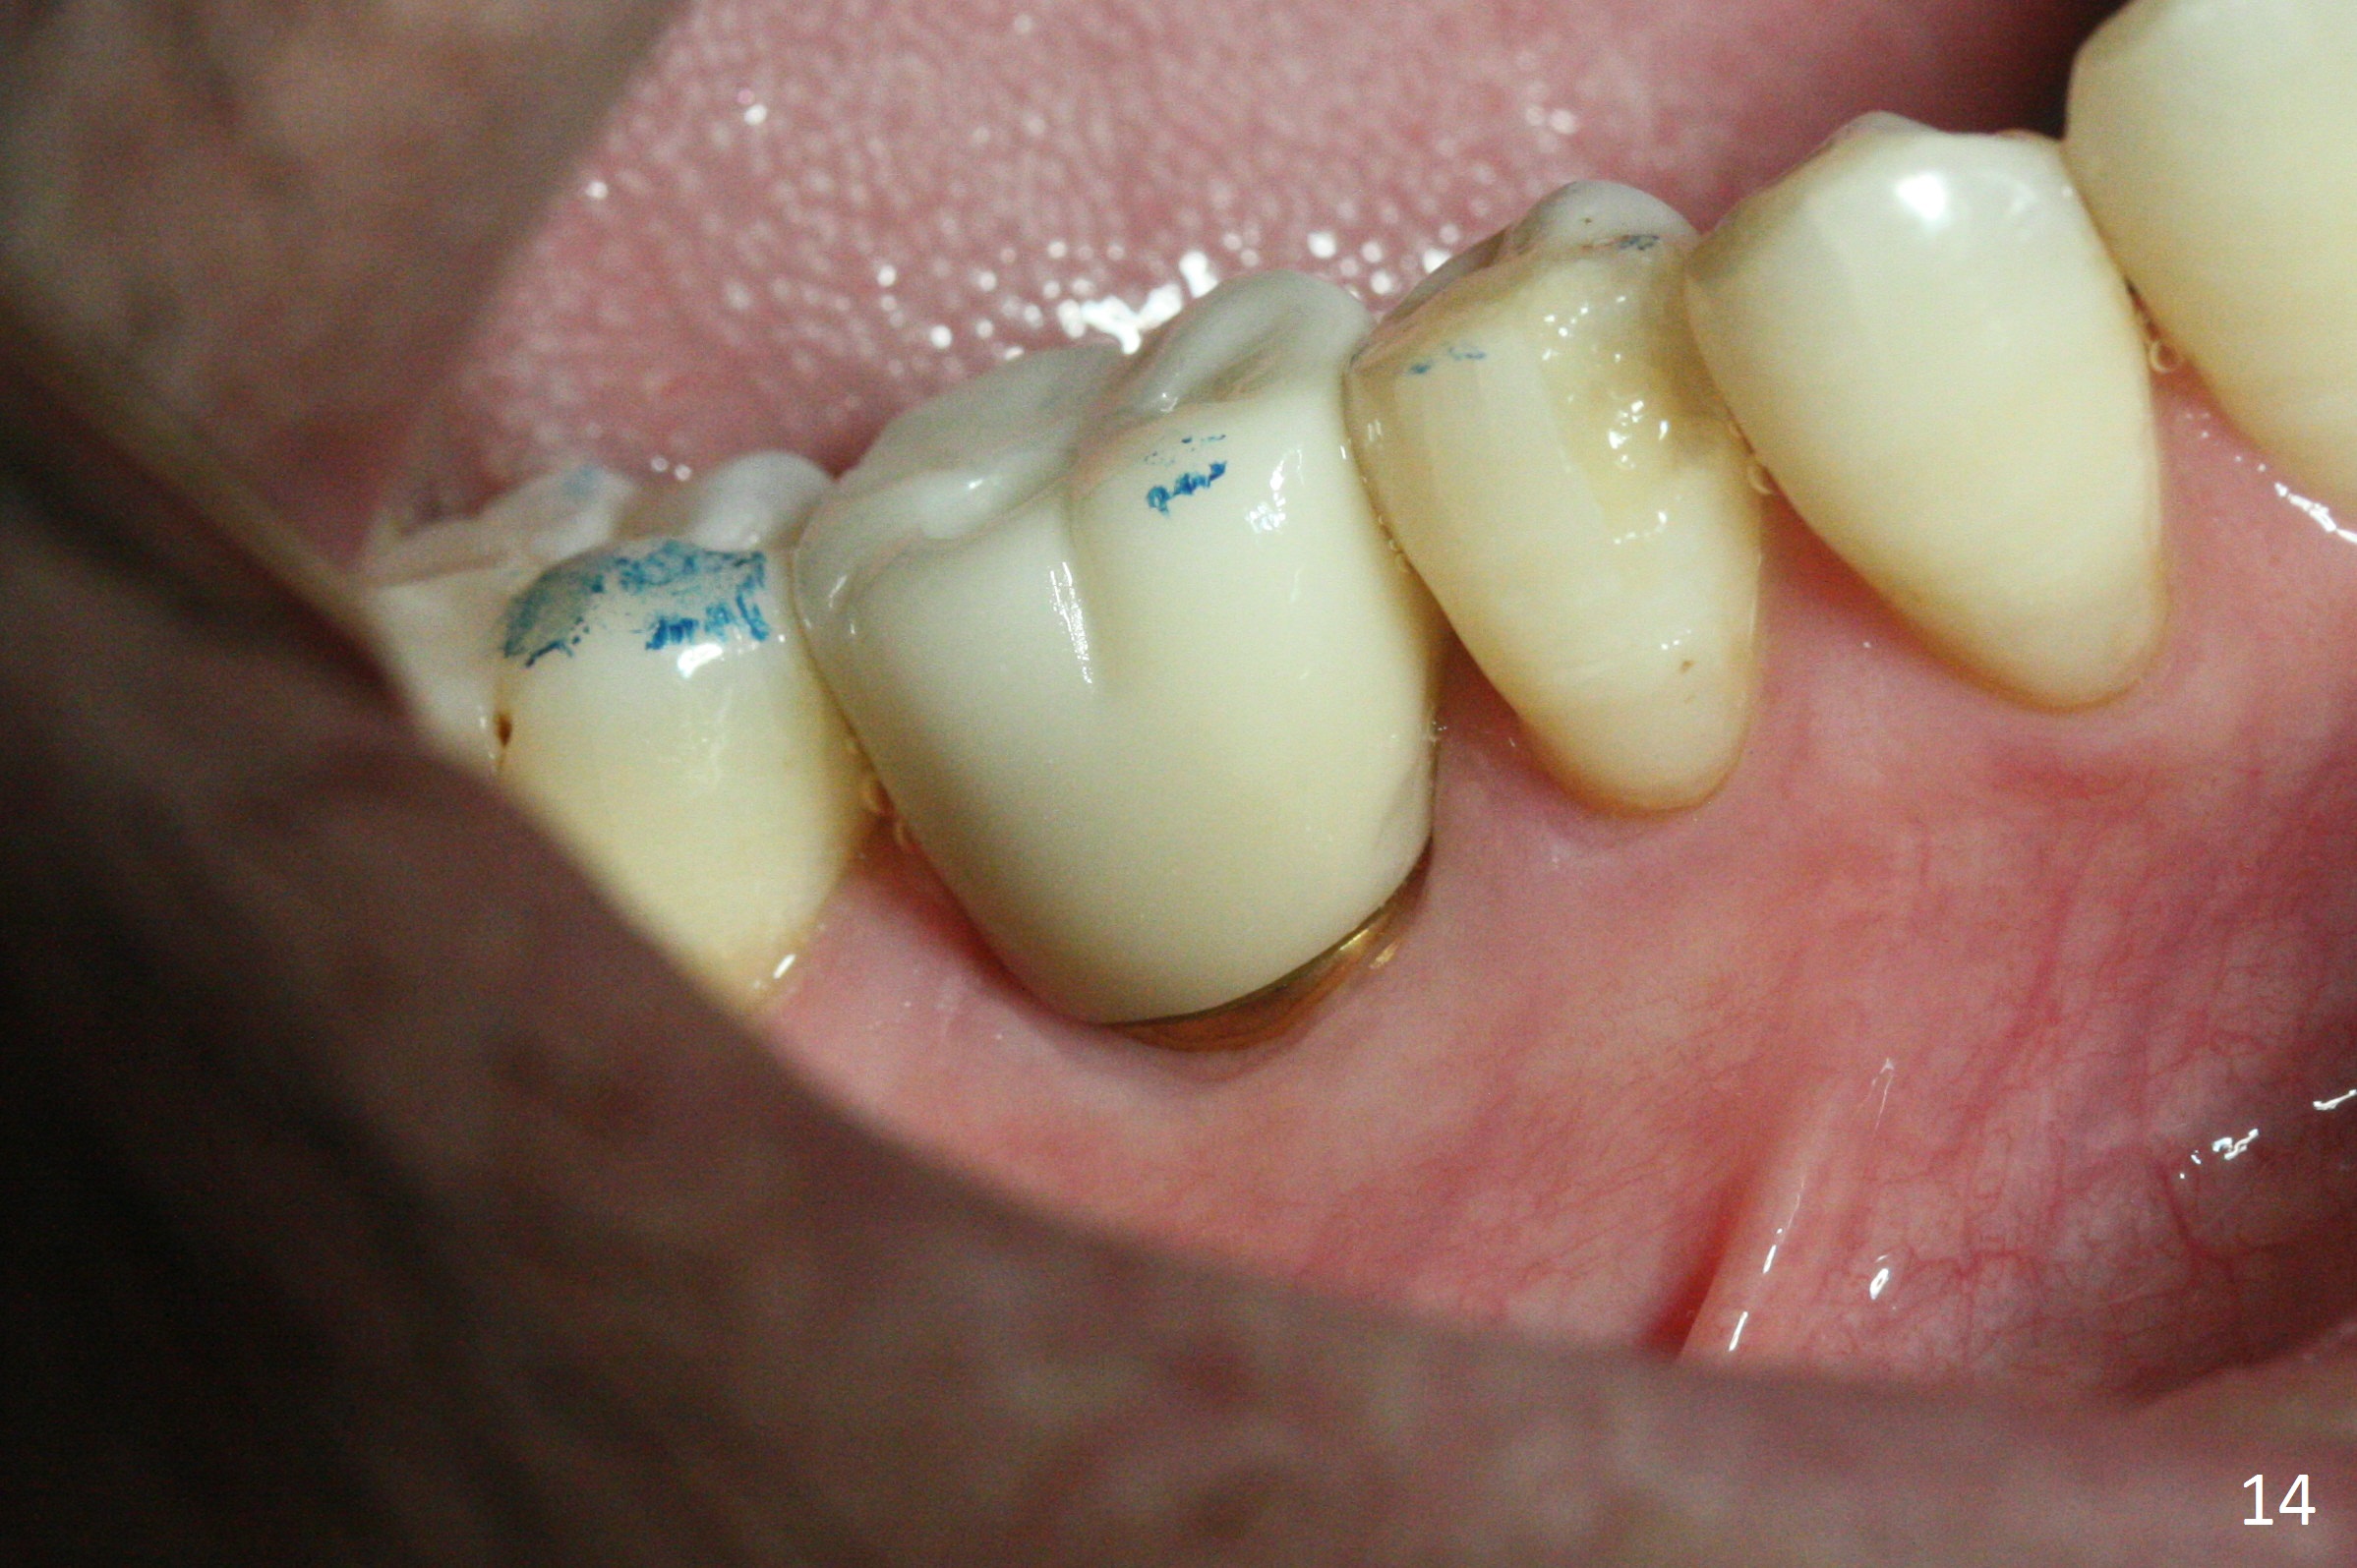

The bone (Fig.10 arrowhead) and soft tissue (Fig.11 *) heal 2 months postop. Gingivectomy is done with Diode prior to impression (Fig.12). The provisional is relined to keep the margin (Fig.13, 2 weeks later) and a permanent crown tries in (Fig.14).